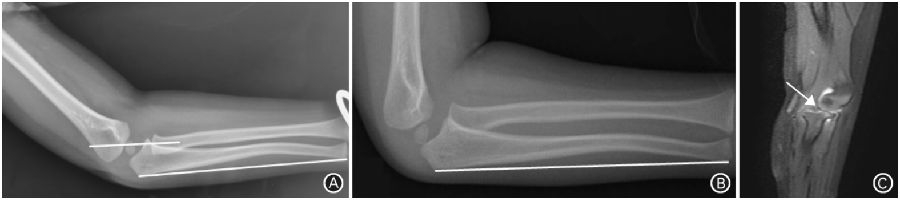

1.5 孟氏骨折

图5 孟氏骨折。A. 伤后即刻侧位X线片示尺骨弯曲骨折,肱桡关节对位对线差,桡骨颈轴线通过肱骨小头上1/3(白色横线),关节软骨不可见;B.伤后4周侧位X线片示明显陈旧孟氏骨折;C.矢状位MRI示肱桡关节之间环状韧带卡压,桡骨头半脱位(箭头所示)